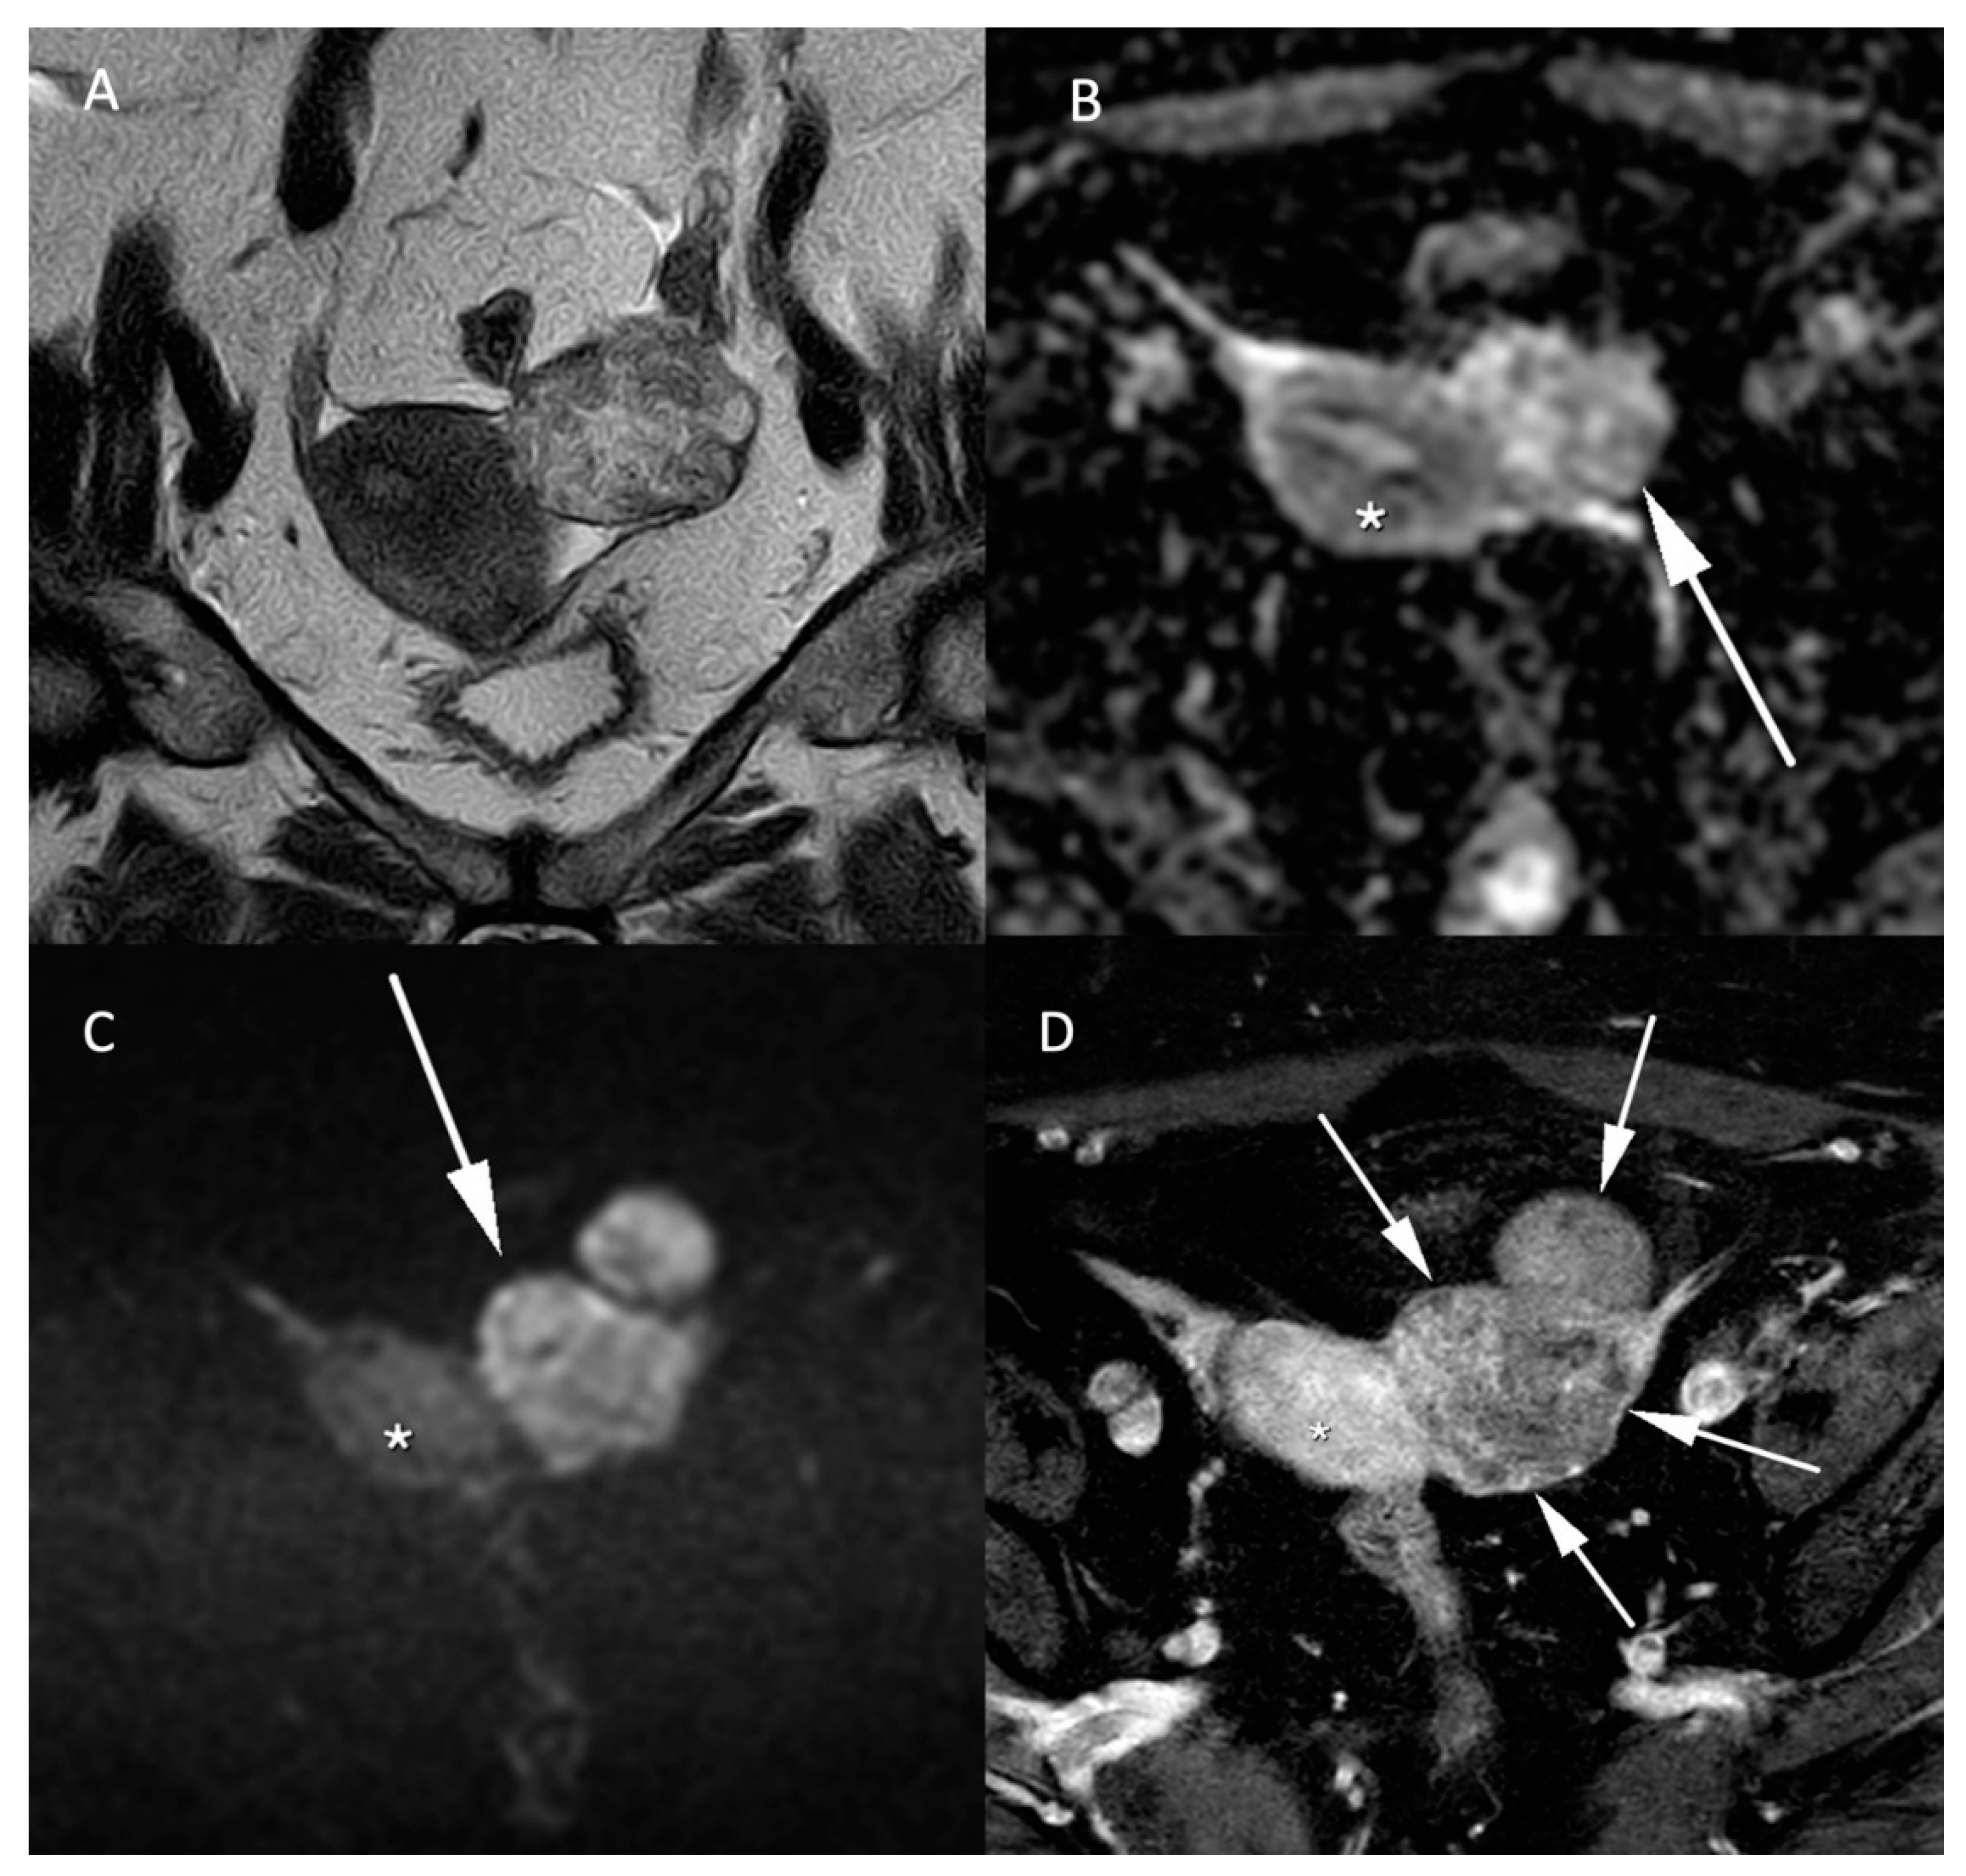

Leiomyosarcomas are rare malignant tumors of the uterus and account for less than 10% of uterine cancers. The differentiation between benign leiomyoma and leiomyosarcoma is essential for the surgical management of these lesions. MRI and especially DWI play an important role in the characterization and management of both tumors. In addition to morphologic specificities of leiomyosarcoma, such as the intermediate T2 signal, nodular borders, hemorrhagic components, “T2 dark” areas and central unenhanced areas [29], DWI-based parameters constitute another essential tool to differentiate benign leiomyoma from leiomyosarcoma. As shown in Figure 4, uterine leiomyosarcoma usually shows low ADC values and increased signal intensity on high b-value DW images compared to the normal myometrium [15]. In the meta-analysis of Virarkar et al. which included 795 patients from eight studies, ADC values were significantly lower in leiomyosarcomas than in leiomyomas [30]. In a recent case-control retrospective study, Wahab et al. proposed a diagnostic algorithm to differentiate leiomyomas from uterine sarcomas based on the presence of lymphadenopathy, higher SI on high b-value images in the mass relative to the endometrium and ADC values inferior to 0.905 × 10−3 mm2/s [31]. The respective sensitivity and specificity of this algorithm to classify the uterine masses were 97% and 99% in a training set of 156 patients, 88% and 100% in a first validation set of 42 patients and 83% and 97% in a second validation set of 59 patients. Focally or globally reduced T2W SI and DWI-based SI lower than the endometrium allows to confidently diagnose the mass as benign [31]. However, this promising approach needs further validation by prospective multicentric studies.

Figure 4.

MR images of a leiomyosarcoma in a 54-year-old woman. (A) voluminous leiomyosarcoma with an intermediary T2W signal and irregular borders (arrow). Part of the leiomyosarcoma demonstrates a diffusion restriction with low (B) ADC values and high signal on the (C) b-1000 sequence. (D) post injection of gadolinium T1W sequence shows the absence of central enhancement consistent with central necrosis. All features are characteristic of malignancy within a leiomyoma.